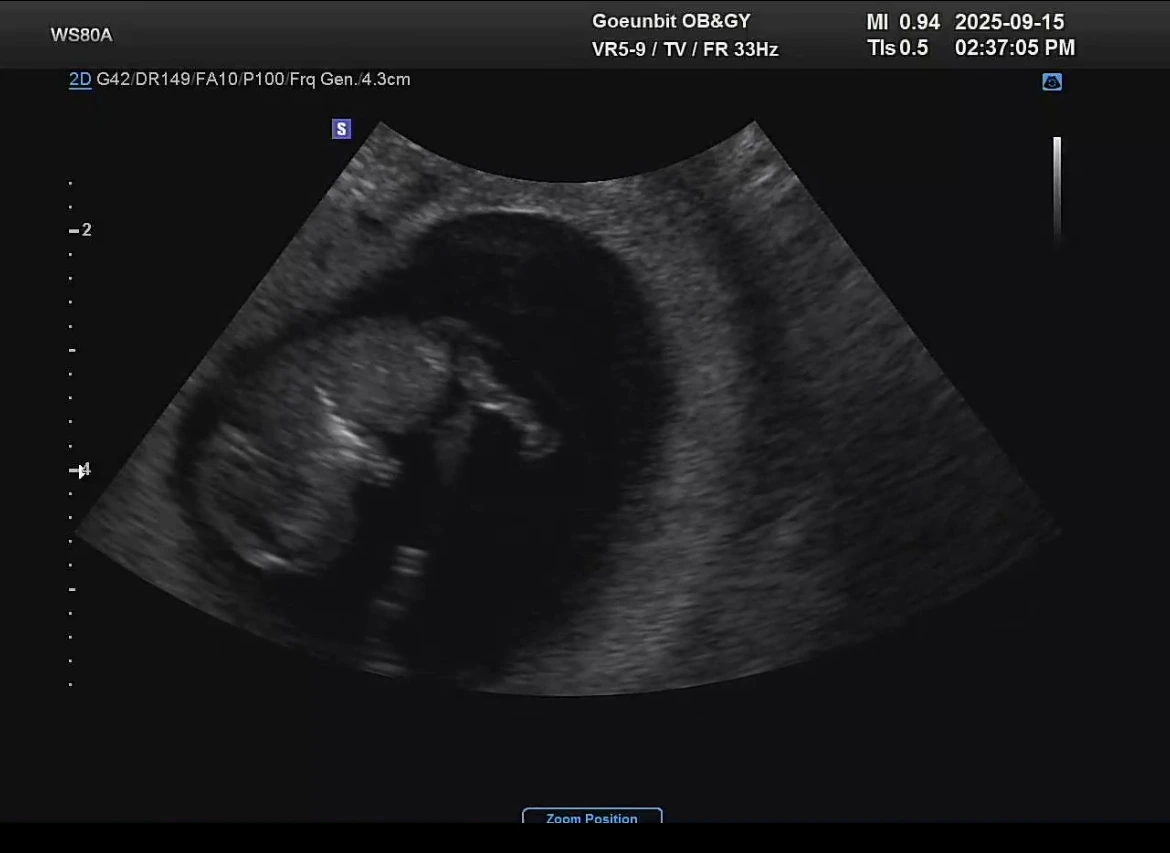

하루하루 반복되는 일상은 똑같은데 활동성이 많이 줄어들다보니 맥아리가 없이 쳐지는 기분이 든다. 제일 귀엽다는 젤리곰 초음파를 보고 와도 설레는 마음이 지속되진 않는다.

그래도 아기는 자신의 발가락을 뽐내며 내 뱃속에서 데굴데굴 잘 굴러 다니고 있다. 막되먹는 생각을 하는 엄마에 비해 퍽 대견한 행보다.